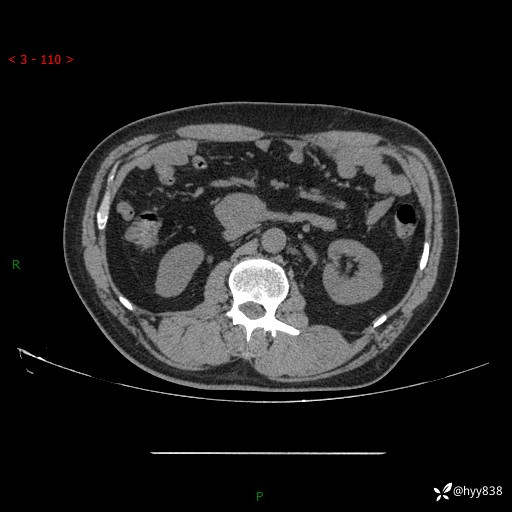

腹部CT平扫